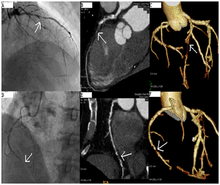

If atheroma, or clots, are protruding into the lumen, producing narrowing, the narrowing may be seen instead as increased haziness within the X-ray shadow images of the blood/dye column within that portion of the artery; this is as compared to adjacent, presumed healthier, less stenotic areas. See the single frame illustration of a coronary angiogram image on the angioplasty page.

CT angiography can act as a less invasive alternative to Catheter angiography. Instead of a catheter being inserted into a vein or artery, CT angiography involves only the injection of a CT-visible dye into the arm or hand via an IV line. CT angiography lowers the risk of arterial perforation and catheter site infection. It provides 3D images that can be studied on computer, and also allows measurement of heart ventricle size. Infarct area and arterial calcium can also be observed (however those require a somewhat higher radiation exposure). That said, one advantage retained by Catheter angiography is the ability of the physician to perform procedure such as balloon angioplasty or insertion of a stent to improve blood flow to the artery.[3]